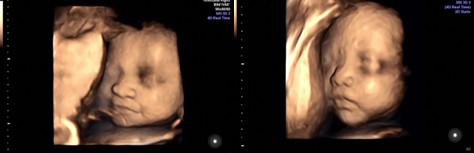

随着探头的移动和金医生细心的讲解,我的心情也慢慢放松下来,探头每移动一个位置,我就自认为是查完了宝宝的一个部位。查着查着宝宝好像累了,不动了,护士将我轻轻扶起,让我喝了点水,吃了块糖,再接着躺下检查。宝宝肯定是吃到了糖果,瞬间变的很活泼,我还看到了他揉眼睛、微笑,真的照的好清楚哦,老公也一直在旁边咧嘴笑。

拿着四维检查单和医生送的照片、U盘,我和老公一边走一边说:“宝宝眼睛挺大呀,鼻子也大,不像爸爸的扁鼻子,还是像妈妈,高高挺挺的,哈哈!”

给好朋友们看照片,第一反映都是说像男孩,长得像爸爸,对我来说,男孩女孩都一样,健康就好。